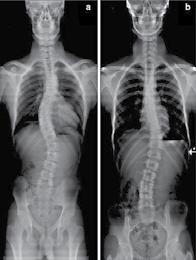

18 콜로라도 타임즈 · 2022년 10월 20일 목요일 · 1049호 교통사고 후유증 / 목 통증 / 목 디스크 / 오십견 / 어깨통증 말초신경장애: 손, 발, 다리의 통증, 저림, 근육약화감, 감각상실 (편)두통 / 불면증 / 어지러움 / 턱관절 장애(TMJ) 척추측만증(Scoliosis) / 척추협착증 / 허리수술 후유증 허리통증 / 허리 디스크 / 관절염 / 좌골신경통 / 고관절, 발목, 손목 통증 ▪ ▪ ▪ ▪ ▪ ▪ ▪ ▪ ▪ 최첨단 목/허리 디스트 치료기기 최신형 디지털 X-ray 시설 Therapeutic Massage ▪초음파, 전기치료 Gonstead Chiropractic 교정치료 치료 진료과목 청소년을 위한 척추교정 프로그램 성장이 빠른 청소년기에 척추가 똑바로 자라야 척추 측만증이 예방됩니다. 성장기의 자녀에게 척추교정으로 바른 자세와 건강한 삶을 선물하세요. 무료 척추검사무료 척추검사 무료 상담무료 상담 무료 상담무료 상담 교통사고 치료 전문 Southern California University of Health Science Doctor of Chiropractic 콜로라도주 척추신경 보드 정회원 캘리포니아주 척추신경과 보드 정회원 National Board 척추신경과 정회원 손석기 D.C. 원장, 척추신경 전문의 chiro1health@gmail.comOpen Hours 월/수/금 9am-6pm 화/목: 2pm-6pm 자동차 보험 건강 보험 상해 보험 교통사고후유증,척추·관절통증,더이상참지마세요!